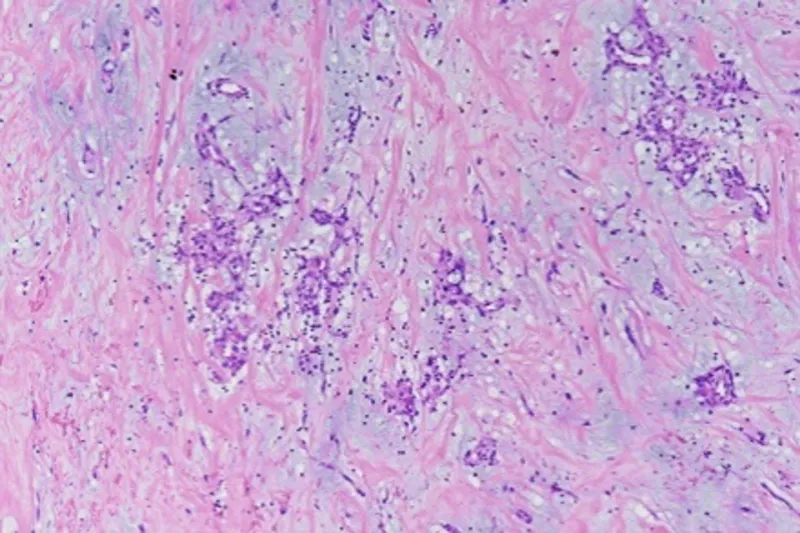

- Pathology: Gelatinous, friable mass ("jelly ball") composed of myxoma cells in a myxoid stroma.

- Histology: Large, vacuolated "spider cells" containing glycogen.